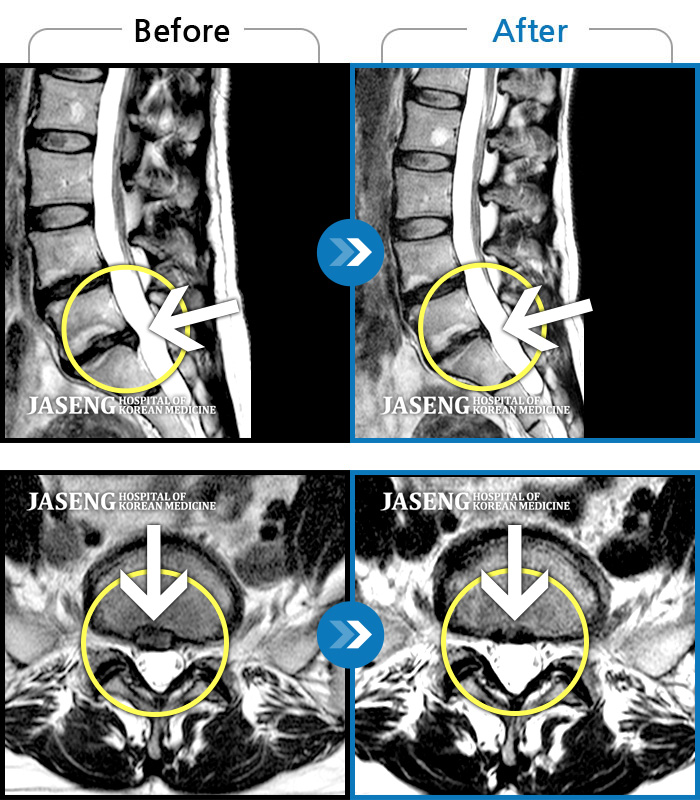

[뱸] 19.11.28~25.05.06

ȯںп Ǹ ǿ ԿǾ, ο ġ ۿ Ƿ ġḦ Ͻñ ٶϴ.